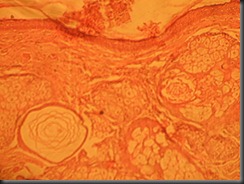

Basal Cell Carcinoma High Resolution Histology Slide

basal cell carcinoma  high resolution histology slide tsnaps

Basal Cell Carcinoma

High Resolution Histology Slide © Tsnaps

Click on the image to enlarge it , you may need to save the image to computer to view it in full zoom once its opened by clicking .

Since it’s a high resolution image ,opening of the image may take time.

Feel Free to use images for educational purposes.

Share us on Facebook if you like our work.